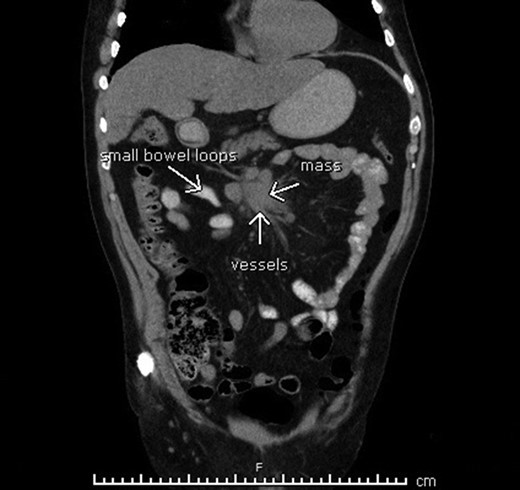

A computed tomography (CT) scan of the abdomen and pelvis was performed (Fig. 2), demonstrating a high-grade mechanical bowel obstruction with transition point in the mid abdomen adjacent to a mesenteric soft tissue mass, most likely in keeping with recurrence of the mesenteric B-cell lymphoma. There was interloop free fluid, mesenteric congestion and gas locules adjacent to the soft tissue mass—thought to represent mesenteric venous gas and bowel ischemia.

Computerized tomography suggesting tumor recurrence and small bowel obstruction.